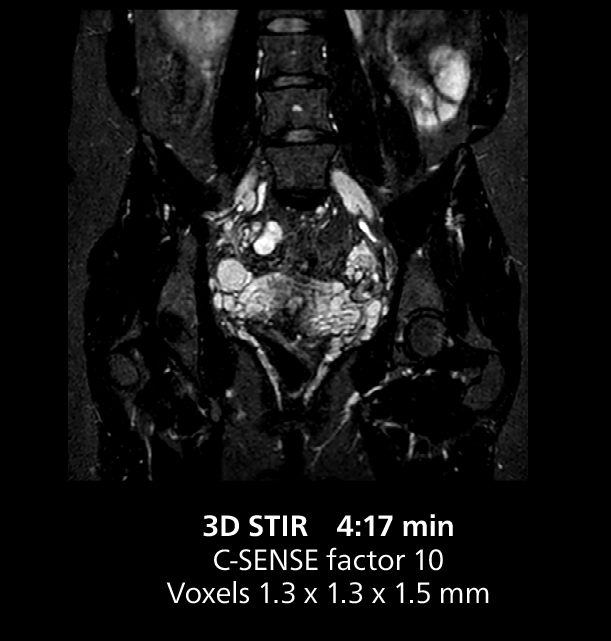

Female pelvis imaging

This MRI case illustrates good resolution and imaging quality obtained within reasonable scan times using the MR 5300 1.5T system with the anterior torso cardiac coil that allows use of a large field of view (FOV).